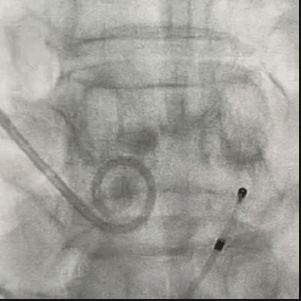

从三叶瓣重度钙化到二叶瓣畸形的根部解剖,从单纯主动脉瓣反流到入路极端迂曲挑战的案例。TaurusOne凭借其优异的柔顺性,支撑力强及内外层双侧裙边的特点,都能从容应对复杂的临床患者解剖结构。从患者的临床选择到术后的长久获益,从手术入路的种类到术中操作的注意事项,从围术期卒中的循证医学到术后的抗凝抗栓用药规范,在线专家共同交流彼此中心的围术期TAVR经验和分享现阶段经导管主动脉瓣置换的诊疗策略。针对当前TAVR领域多个热点学术问题进行了热烈的讨论,现场可谓精彩纷呈、高潮迭起。专家们纷纷借此契机相互交流探讨,分享各自的单中心经验,力求进一步提升TAVR手术的安全性和有效性,为主动脉瓣相关疾病的患者带来长远综合获益。